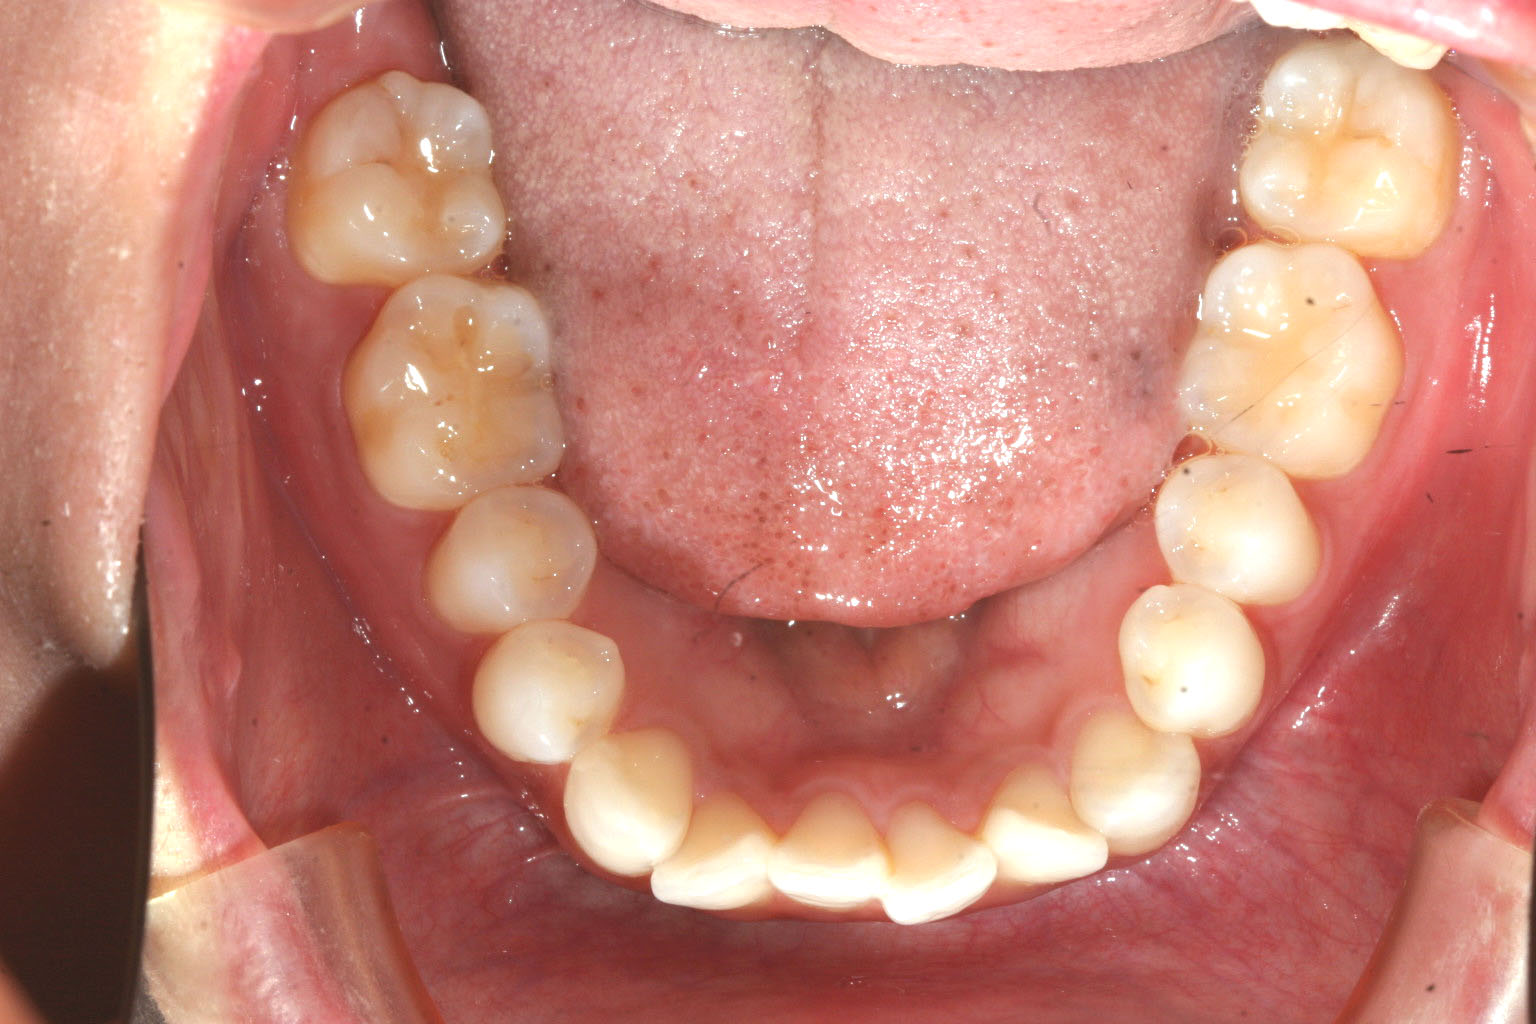

下顎にも少し叢生が見られます。

下顎もバッチリですね!